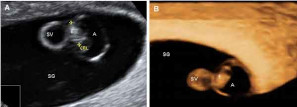

En la ecografía precoz ya puede verse el embrión en forma de punto blanco y en su interior el corazón latiendo. Los más modernos aparatos de ultrasonidos también permiten además de ver en colores el corazón, escuchar su latido. Lo idóneo es realizar esta ecografía por vía vaginal, ya que por vía abdominal es aún pronto para visualizar el embrión.

- El embrión ya mide entre 2 y 4 milímetros en la semana 6 de embarazo.

- Esta medida es la longitud desde la cabeza (el polo cefálico) hasta el final de la columna vertebral (el polo caudal). Por eso a esta medida se le llama LCC en español (longitud cráneocaudal) o bien LCN longitud cráneo nalga o CRL en inglés ("crown-to-rump length"). Es la más utilizada para medir al embrión, obviando la distancia hasta los pies, ya que las piernas generalmente están dobladas y sesgan la longitud real del bebé.

- El corazón ya está latiendo, signo que se puede apreciar mediante ecografía. Es un corazón muy pequeño que late muy deprisa, entre 120 y 160 latidos por minuto